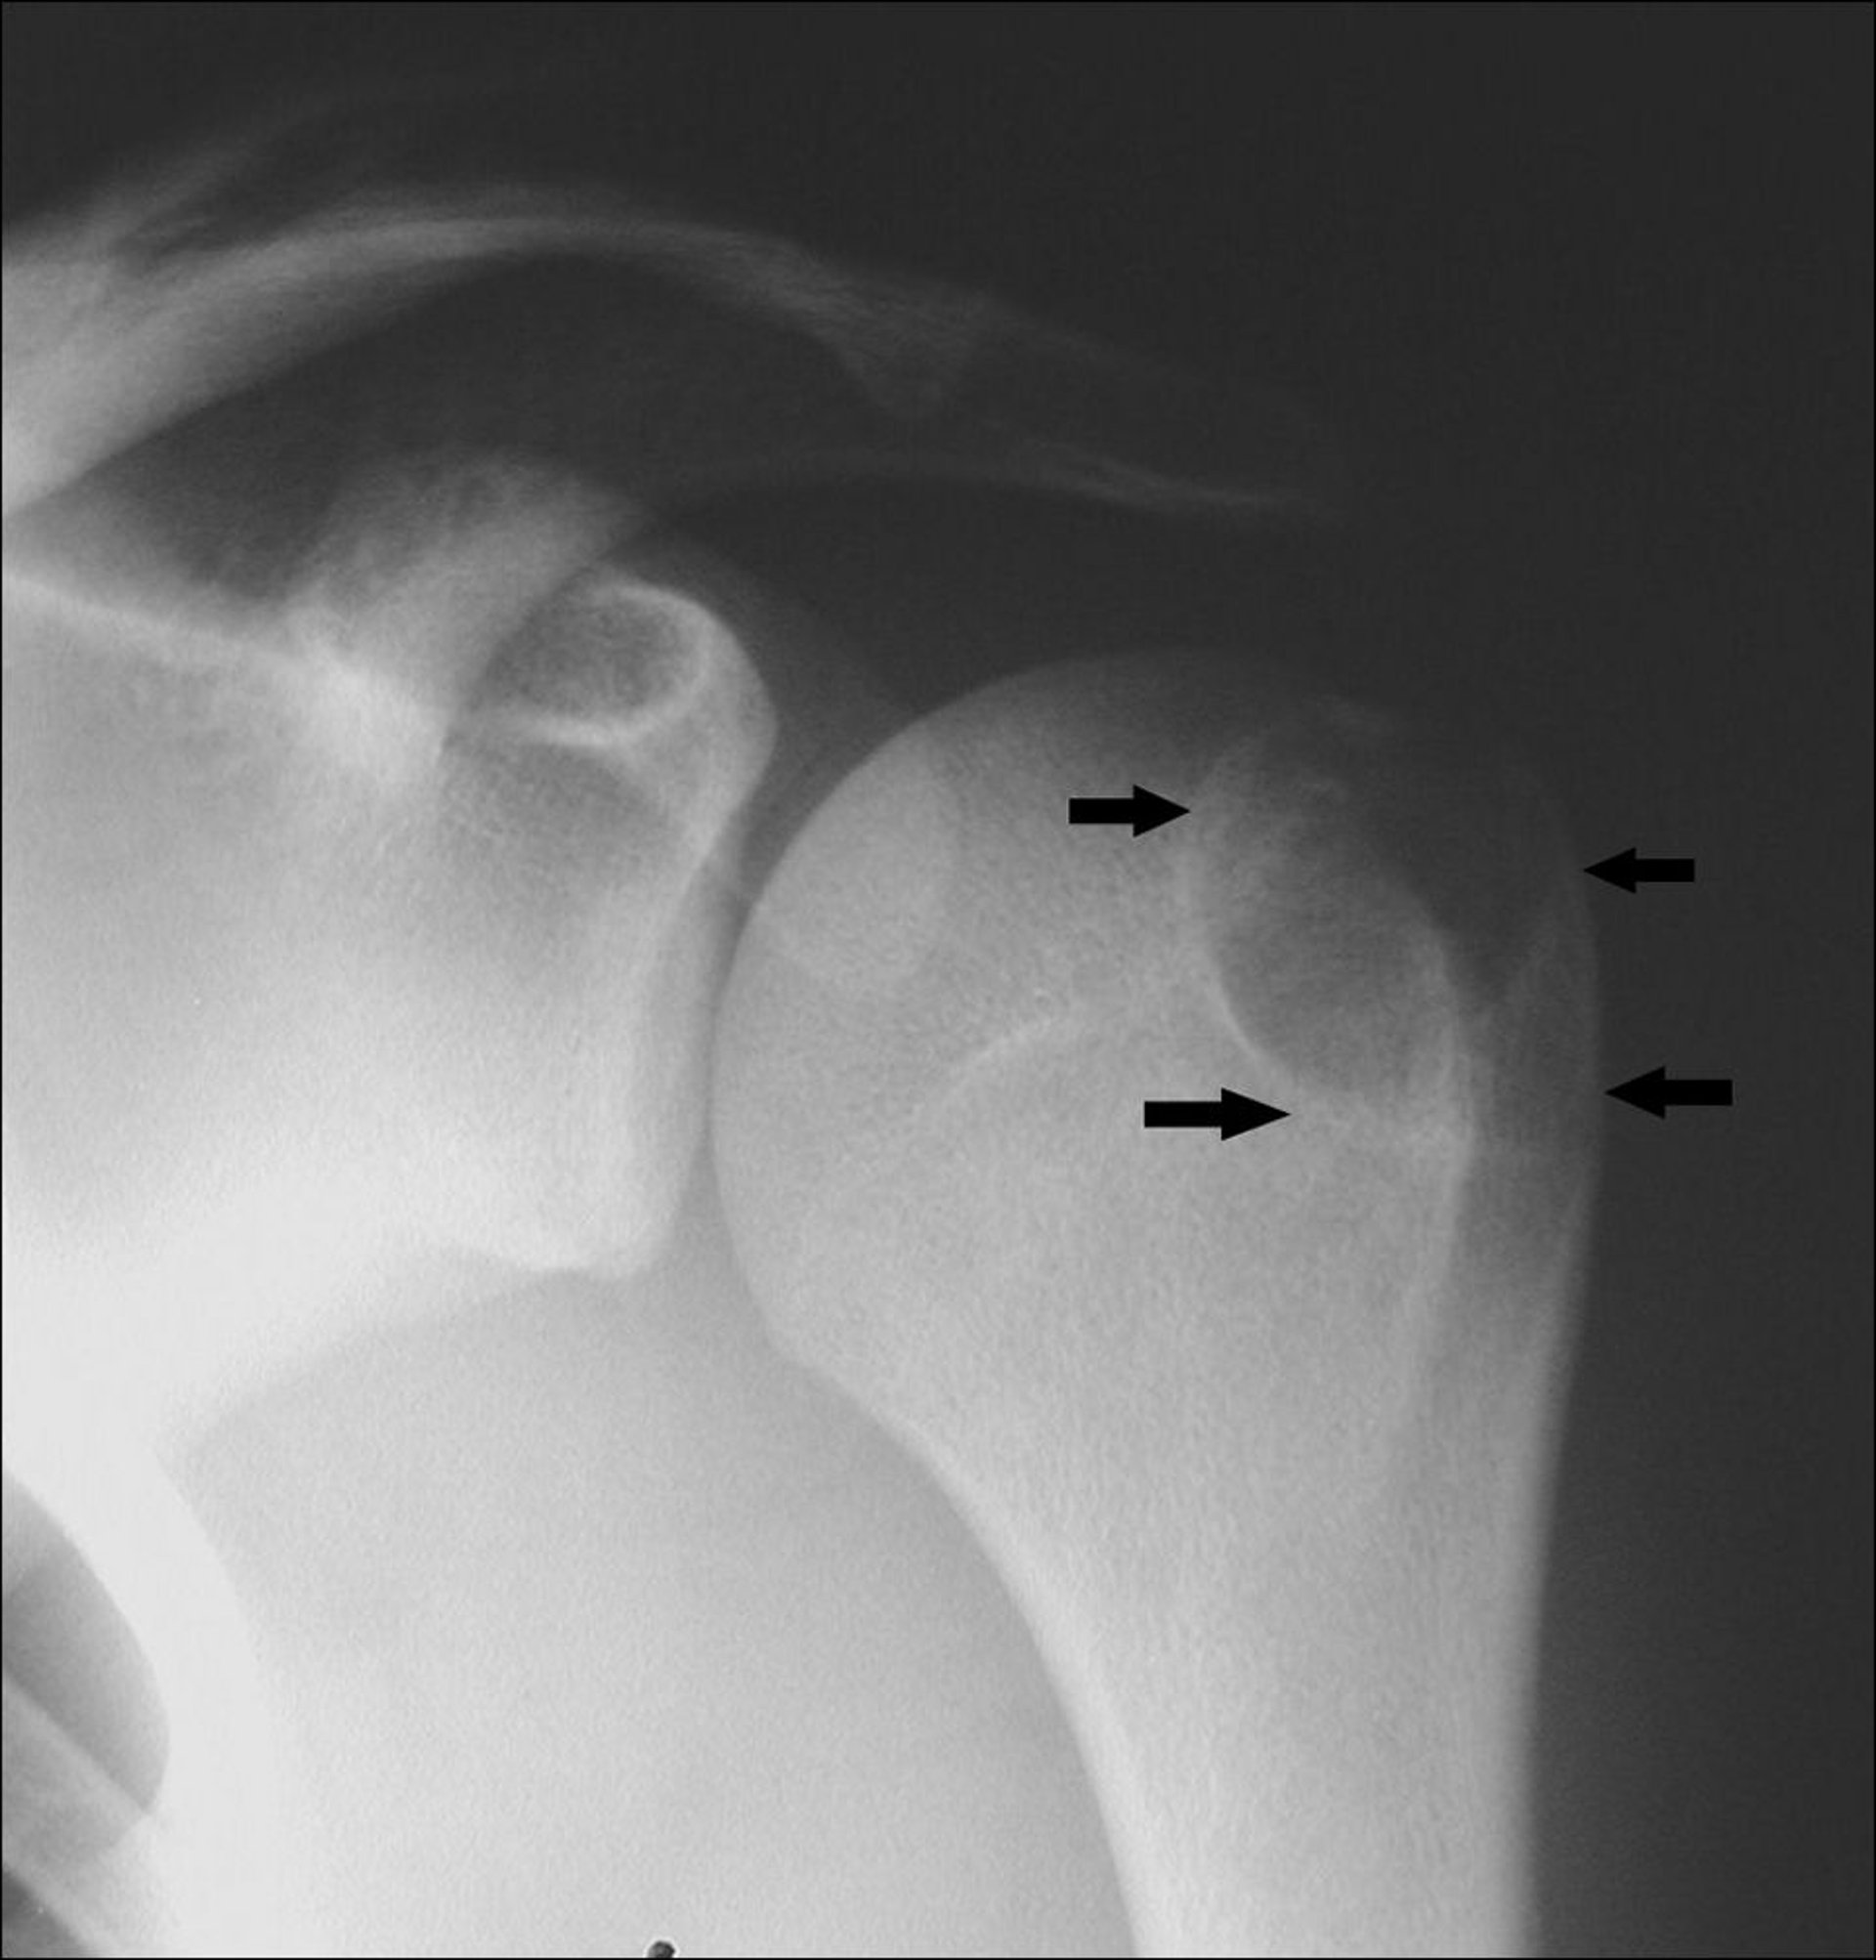

Radiografia della spalla che mostra un condroblastoma all’estremità dell’osso del braccio (frecce).

Per gentile concessione di Michael J. Joyce, MD e Hakan Ilaslan, MD.

Se non trattati, questi tumori possono continuare a crescere, distruggendo l’osso e l’articolazione. Pertanto il trattamento consiste nella rimozione chirurgica e nell’inserimento di un innesto osseo (trapianto di tessuto osseo da un osso all’altro) che sostituisce l’osso prelevato. Il materiale da innestare può provenire da tessuto osseo rimosso dal bacino del paziente (autoinnesto), da tessuto osseo elaborato proveniente da un’altra persona (alloinnesto) o da un sostituto osseo sintetico. Talvolta, questi tumori si ripresentano dopo l’intervento chirurgico.